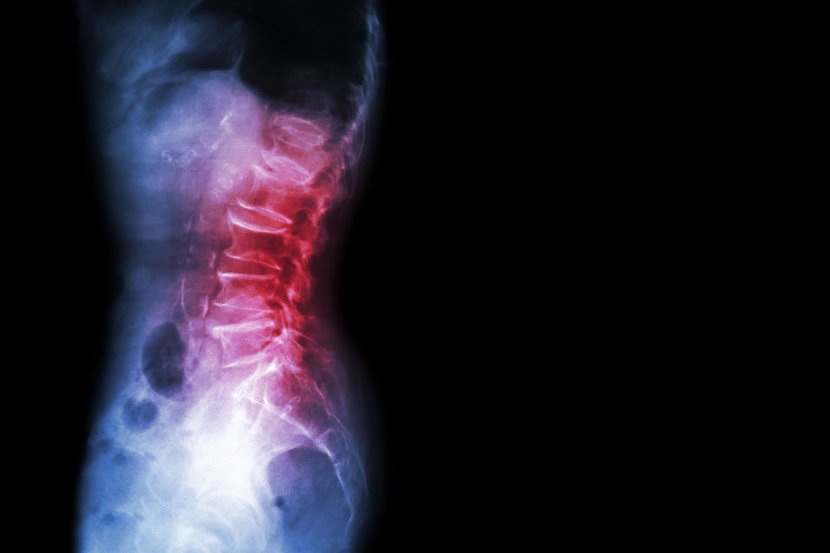

Spondilolisteza je stanje kičme koje uzrokuje bol u donjem delu leđa, a javlja se kada jedan od pršljenova (kosti kičme) sklizne sa svog mesta na pršljen ispod njega. U većini slučajeva  nehirurški tretman može da ublaži simptome, a ako je u pitanju teži oblik spondilolisteze, operacija je u većini slučajeva uspešna.

Spondilolisteza je nestabilnost kičme, što znači da se pršljeni pomeraju više nego što bi trebalo jer se dešava da gornji pršljen klizi sa svog mesta na pršljen ispod. Na taj način može da izvrši pritisak na nerv, što može da izazove bol u donjem delu leđa ili nogu.

• Rendgen kičme pomaže zdravstvenim radnicima da vide da li je pršljen na svom mestu ili je skliznuo na pršljen ispod

• CT skeniranje ili MRI skeniranje može da bude neophodno kako bi se kičma videla detaljnije ili da bi se videlo meko tkivo kao što su diskovi i nervi.